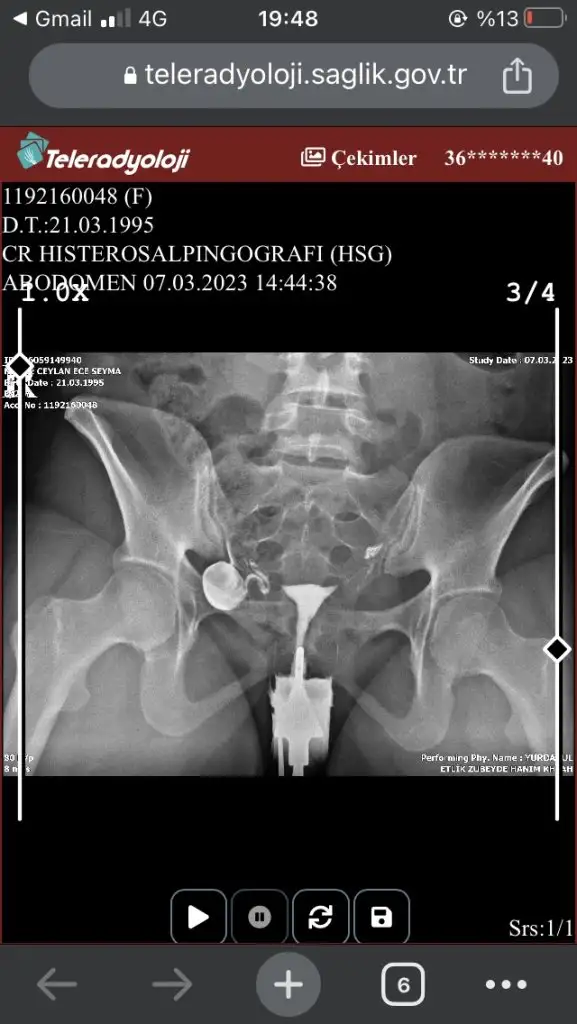

Canım benim ultrasonda görmüştü adetken. Bende korkmuştum. Ama sonrasında öyle bir şey hsg çekilince olmadığı anlaşıldı. Ama senin hsg de çıkmış. Ama sen yine sonuçlarınla başka doktorlara git. Birde hsg filmide çok önemli. İyi bir yerde mi çekildin

Devlet hastanesinde çekildim kadın doğum hastanesinde.